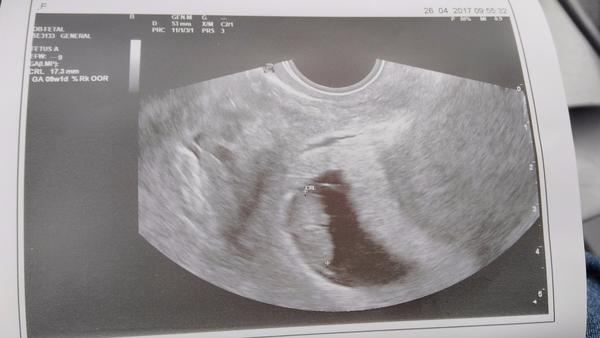

Konečne mam výsledky z krvi od dr na hcg hormon. Som tehotna 🙂 HCG 475 jednotiek, ze to vyzera na 4tt...nie je to malo??? Ms som mala 13 mar a ovu bola 7-8 aprila

no ak dobre ratam ( to len tak zaokruhlujem ), tak si mala cyklus dlhysi a teda mala 3t do ovulky a potom presli zhruba 2t, cize sice to dokopy je 5tt, ale babo je velke presne ako v tom cykle, ktory som popisala na zaciatku, cize velkostne je na 4tt. a teda aj HCG nestupa kazdej rovnako. tam su tiez pomerne velke referencne hodnoty.

@ejuska2586 jj mam uz aj potvrdene tehu od dr 😉 v utorok idem znovu na krv a na utz 🙂